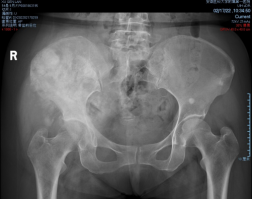

术前影像

穿刺活检提示骨盆软骨肉瘤

日前,安医大一附院骨病骨肿瘤外科胡勇教授团队成功完成一例复杂骨盆Ⅰ+Ⅱ+Ⅲ+Ⅳ区肿瘤切除与3D打印组配式半骨盆假体重建手术。患者为女性,53岁,下腰痛半年余,右侧臀部膨隆,右侧下肢轻度浮肿。右侧髂棘髂窝及臀部可触及巨大肿物,压痛明显,右髋外展前屈活动受限,右侧大腿感觉麻木,右足感觉运动正常。骨盆肿瘤切除重建是骨科专业中难度极大、风险极高的手术。骨盆肿瘤约占原发骨肿瘤的3%~4%,其中以软骨系统肿瘤最为多见,其次为骨巨细胞瘤、成骨肉瘤等,儿童尤文肉瘤亦好发于骨盆。